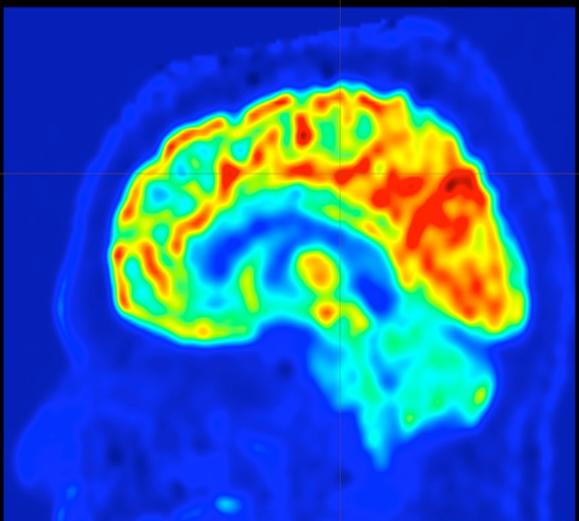

A brain map, created by a new approach developed at UVA, to guide surgery to prevent epilepsy seizures.

• Developed an advanced imaging approach that could let surgeons determine the best target in the brain to stop epilepsy seizures.